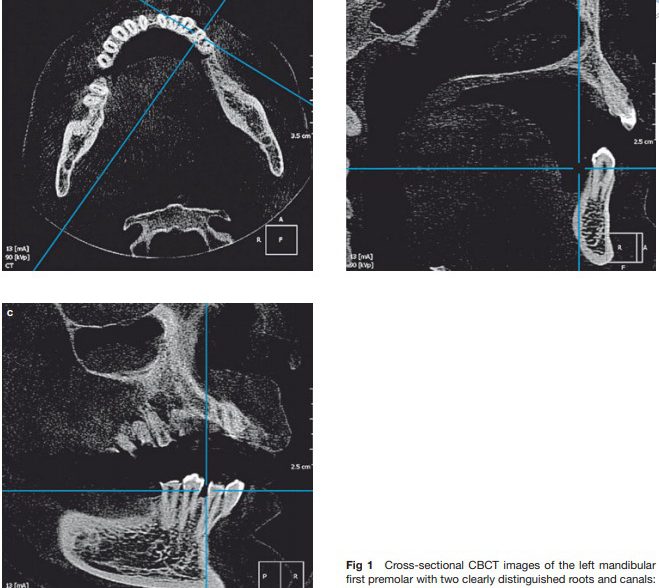

Evaluation By CBCT Of Root and Canal Morphology in Mandibular Premolars in an Iranian Population

Evaluation of CBCT of root